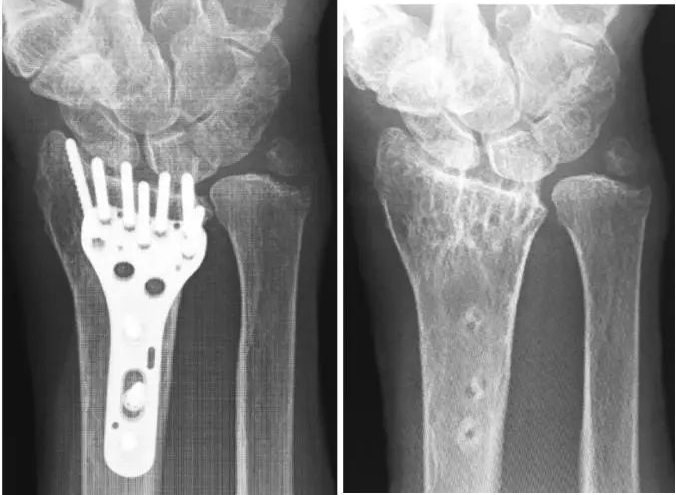

骨科必备技能:桡骨远端骨折掌侧钢板固定新技巧 拇长伸肌(EPL)肌腱损伤是桡骨远端骨折修复的主要并发症。EPL肌腱损伤的危险因素是突出的背侧螺钉、直接的术中钻孔损伤和/或背侧屋顶碎片。…